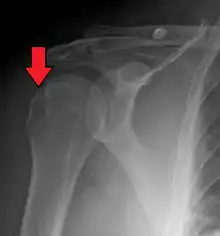

Hill–Sachs lesion post-shoulder dislocation

X-ray at left shows anterior dislocation in a young man after trying to get up from his bed. X-ray at right shows same shoulder after reduction and internal rotation, revealing both a Bankart lesion and a Hill-Sachs lesion.

Diagnosis can be suspected by history and physical examination which is usually followed by imaging. Because of the mechanism of injury, apprehension of anterior dislocation is common with provocative maneuvers. Hill–Sachs lesions have been classified as "engaging" or "non-engaging", with engaging lesions defined by the ability of the glenoid to sublux into the humeral head defect during abduction and external rotation. Engaging dislocations have a higher risk of recurrent anterior dislocation, and their presence can help guide surgical management.[2] Imaging diagnosis conventionally begins with plain film radiography. Generally, anteroposterior (AP) radiographs of the shoulder with the arm in internal rotation offer the best yield while axillary views and AP radiographs with external rotation tend to obscure the defect. However, pain and tenderness in the injured joint make appropriate positioning difficult and in a recent study of plain film x-ray for Hill–Sachs lesions, the sensitivity was only about 20%. i.e. the finding was not visible on plain film x-ray about 80% of the time.[3]